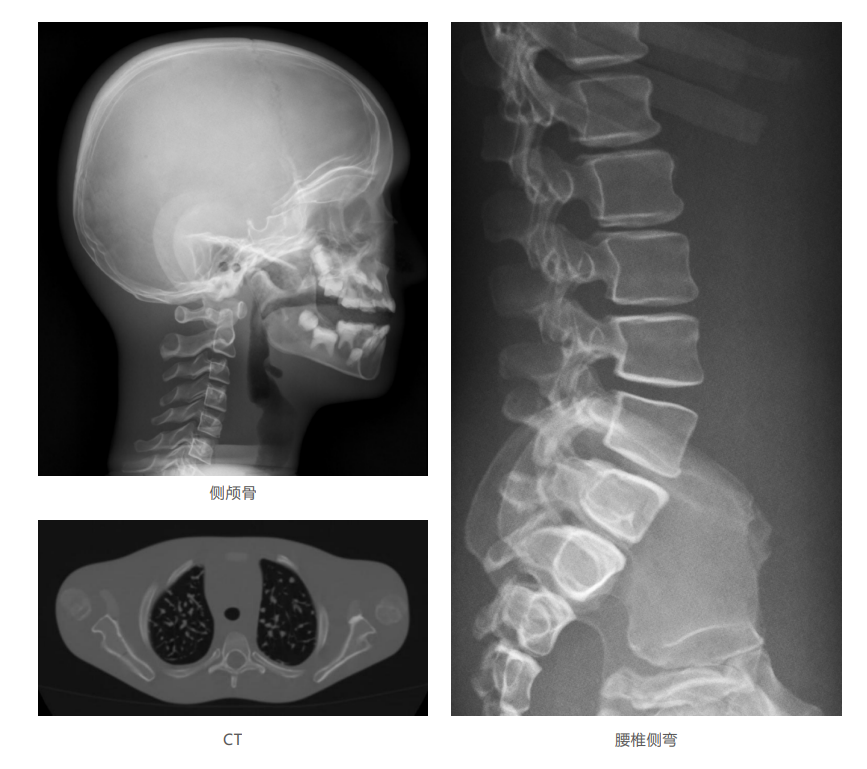

模體掃描成像圖: